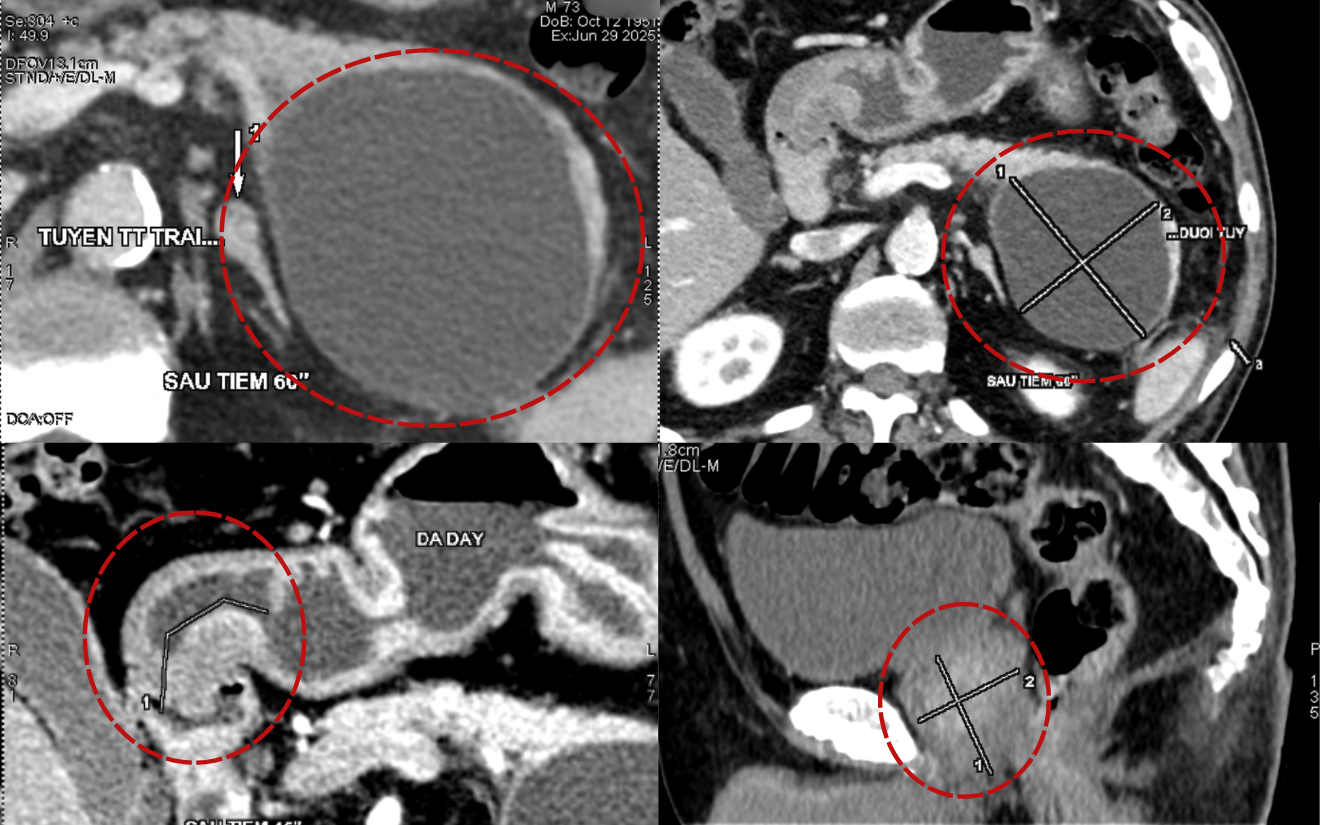

CT 촬영 결과, 환자는 다발성 소화기 손상이 확인되었습니다.